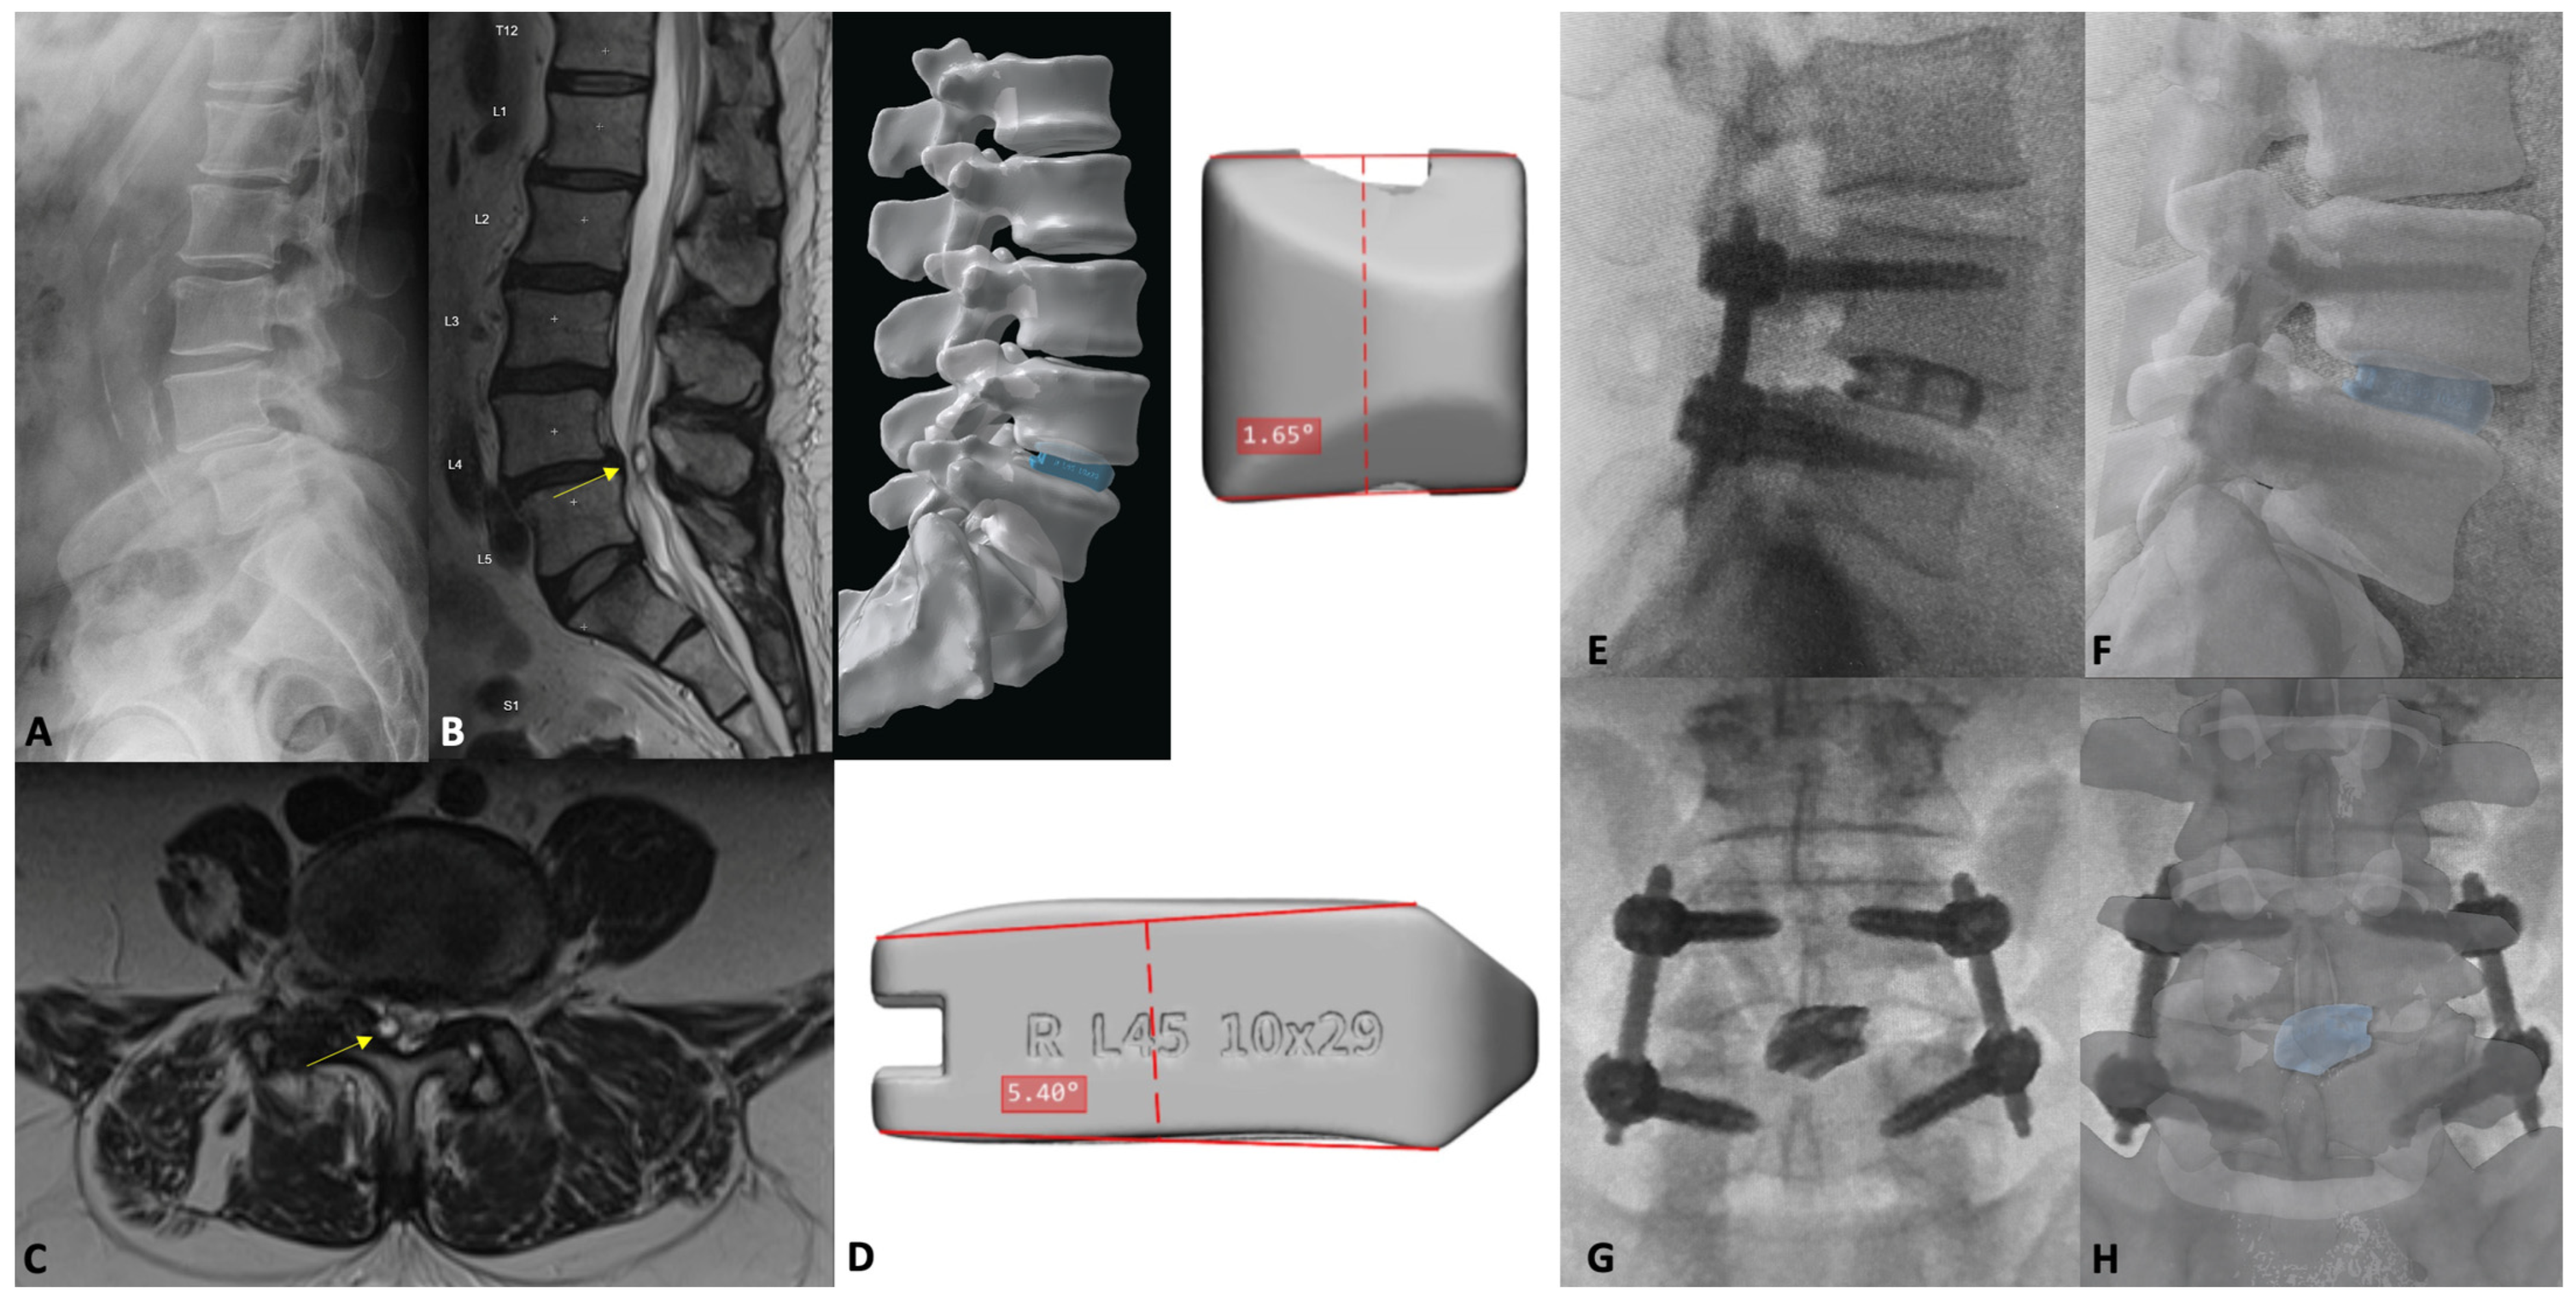

7. Patient-Specific Lumbar Interbody Fusion

7.1. Introduction

7.3. Patient-Specific Implants

- Mobbs, R.J.; Coughlan, M.; Thompson, R.; Sutterlin, C.E.; Phan, K. The utility of 3D printing for surgical planning and patient-specific implant design for complex spinal pathologies: Case report. J. Neurosurg. Spine 2017, 26, 513–518. [Google Scholar] [CrossRef] [PubMed]

- Mobbs, R.J.; Choy, W.J.; Wilson, P.; McEvoy, A.; Phan, K.; Parr, W.C.H. L5 En-Bloc Vertebrectomy with Customized Reconstructive Implant: Comparison of Patient-Specific Versus Off-the-Shelf Implant. World Neurosurg. 2018, 112, 94–100. [Google Scholar] [CrossRef] [PubMed]

- Pesante, B.D.; Wellington, I.J.; Eastlack, R.K.; Singh, H. Multilevel Customized 3D-Printed Titanium Alloy Interbody Cages used to Treat Congenital Scoliosis: A Case Report. J. Orthop. Case Rep. 2023, 13, 58–64. [Google Scholar] [CrossRef]

- Phan, K.; Sgro, A.; Maharaj, M.M.; D’Urso, P.; Mobbs, R.J. Application of a 3D custom printed patient specific spinal implant for C1/2 arthrodesis. J. Spine Surg. 2016, 2, 314–318. [Google Scholar] [CrossRef] [PubMed]

- Thayaparan, G.K.; Owbridge, M.G.; Thompson, R.G.; D‘Urso, P.S. Designing patient-specific solutions using biomodelling and 3D-printing for revision lumbar spine surgery. Eur. Spine J. 2019, 28, 18–24. [Google Scholar] [CrossRef] [PubMed]

- Fernandes, R.J.R.; Gee, A.; Kanawati, A.J.; Siddiqi, F.; Rasoulinejad, P.; Zdero, R.; Bailey, C.S. Evaluation of the contact surface between vertebral endplate and 3D printed patient-specific cage vs commercial cage. Sci. Rep. 2022, 12, 12505. [Google Scholar] [CrossRef] [PubMed]